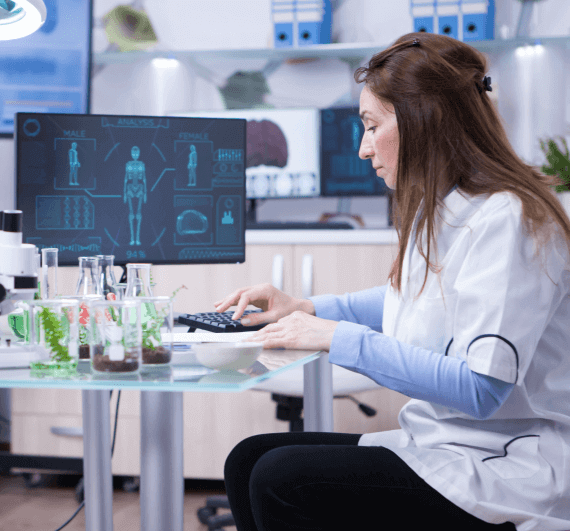

Our laboratory products are of the highest quality

Qualified doctors

There are many variations of passages of Lorem Ipsum available, but the majority have suffered alteration some form, by injected humour, or randomised

Helpful test tips

There are many variations of passages of Lorem Ipsum available, but the majority have suffered alteration some form, by injected humour, or randomised